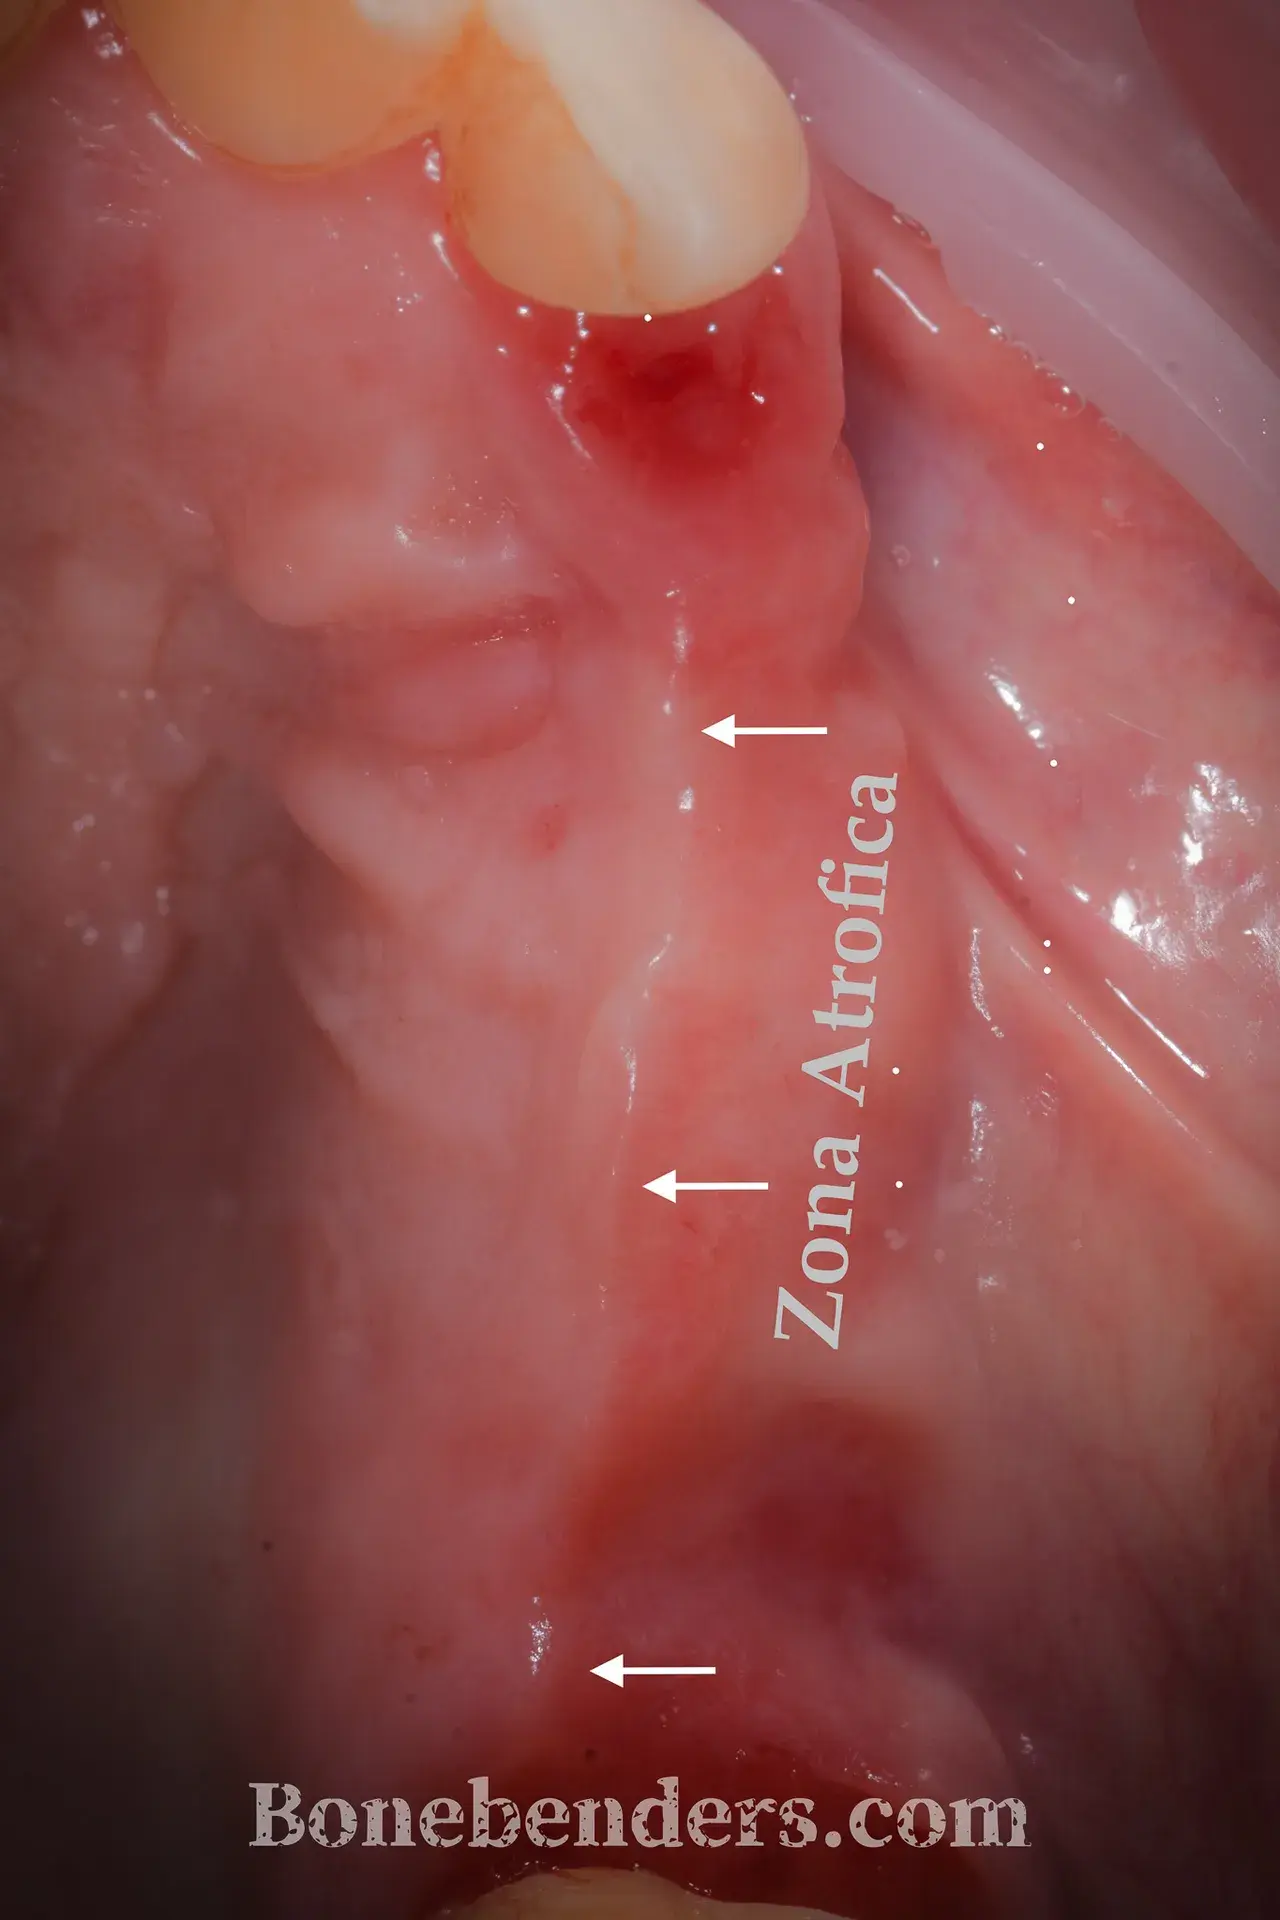

9 casi documentati con fotografie cliniche prima e dopo il trattamento. Ogni caso include la descrizione della tecnica, i tempi di guarigione e i riferimenti scientifici.